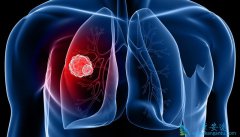

• 通常来说发展到肺癌晚期还能活多久

通常来说发展到肺癌晚期还能活多久

每一个患有 肺癌 的人,在疾病治疗的过程中最担心的事情就是疾病到底能不能治好,如果治不好的话,这一疾病到底会在什么时候会夺取自己的生命。现在就这针对于肺癌患者最关心的该如何通过治疗延长生命这一问题来进行回答。究竟 肺癌晚期还能活多久 ?   ...